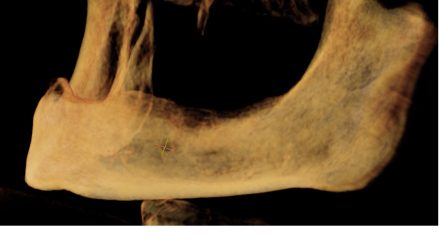

• I have never placed an immediate implant before but I think I found a good first case.

Patient is a 40 year male with a low smile line. Here is my proposed implant site.

I am planning on placing a 4.2×13 implant direct legacy 3. My current plan is to drill to a 2.8 osteotomy and then place the implant and hope for enough primary stability.